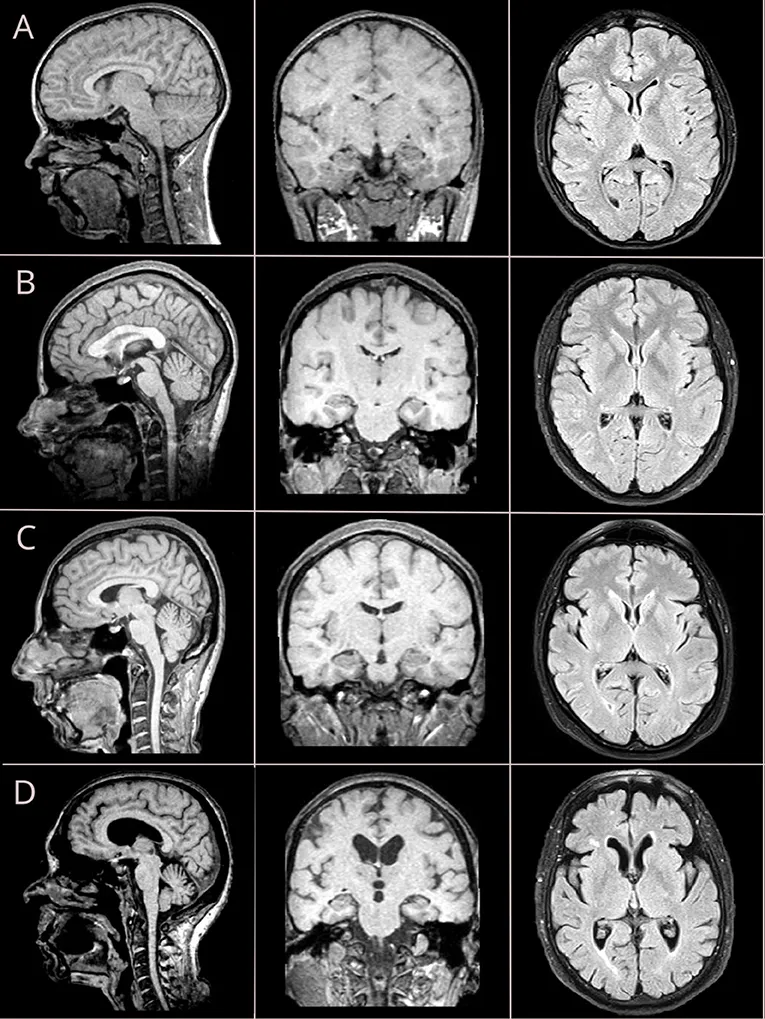

Nervous System ("Brain Fades"):

- Structural Changes:

- Mild cortical atrophy.

- Ventricular enlargement (often compensatory).

- White Matter: Changes evident as leukoaraiosis.

- Brain atrophy involves neuronal loss, ventricular enlargement, and potential plaque/tangle formation.